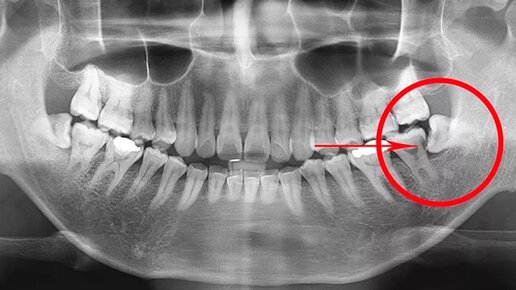

ПОЧЕМУ зубы мудрости растут криво?